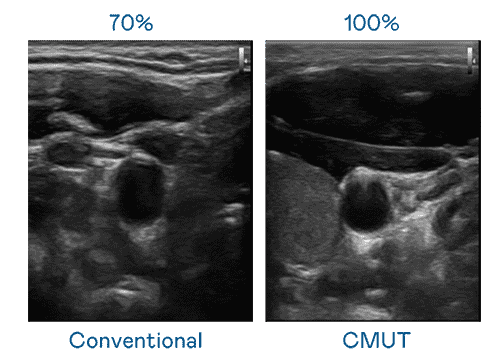

CMUT 技术是一种用电容式微机电元件来产生超音波讯号的技术。。。。与传统 PZT 压电式技术相比,,CMUT 频宽增加 30%,,,更宽频的超音波讯号让影像解析度大幅提升,,,是实现高影像品质医疗超音波扫描、、促进精准医疗发展的关键技术。。

大频宽带来超清晰影像

超音波影像的解析度高低,,首先取决于探头能发出的讯号频宽。。。杏悦2 CMUT 可提供高清晰的超音波讯号,,,提供高频宽、、、、高灵敏度、、影像纹理细节更高的超音波影像,,,,协助医护人员缩短影像判读时间及利用精准的医疗影像进行诊断。。。。